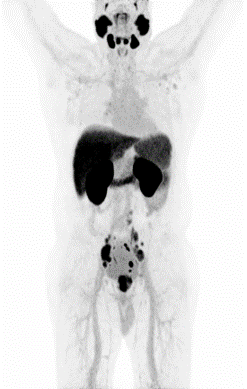

Partial nml and melanoma PET scan